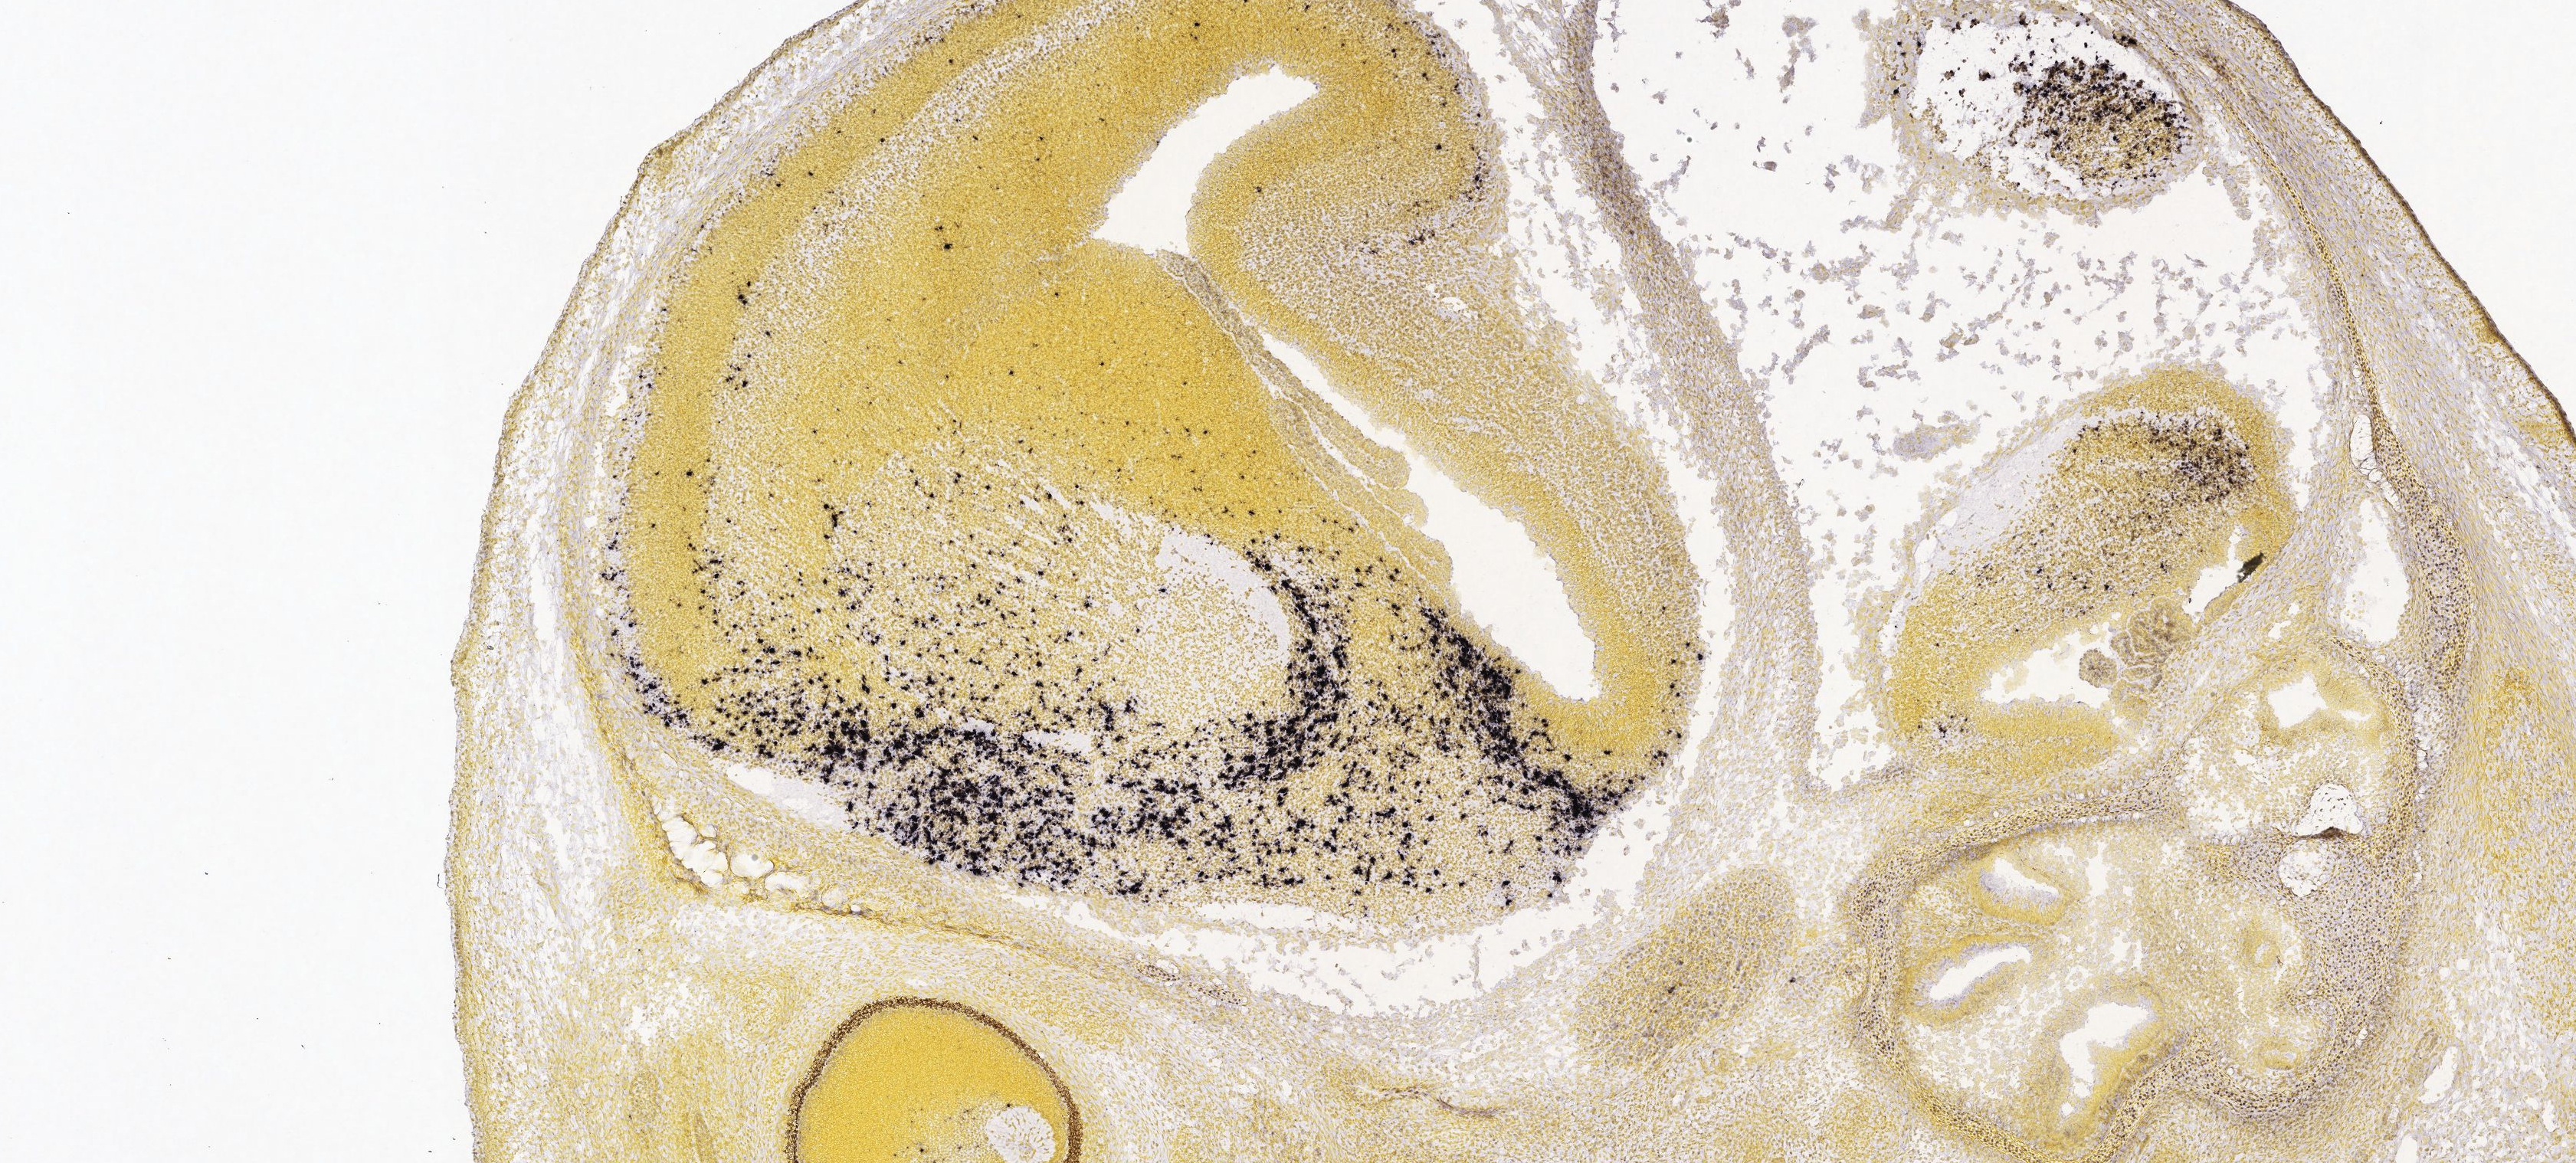

신경계에서는 주로 시상하부의 복내측핵에 위치한 신경분비세포에서 생산된다. 이 세포들은 정중융기를 통해 뇌하수체 문맥계로 소마토스타틴을 방출하여, 뇌하수체 전엽에서의 성장 호르몬(GH)과 갑상선 자극 호르몬(TSH) 분비 조절에 관여한다.[27] 이 외에도 궁상핵, 해마, 뇌간의 고립로핵 등 중추 신경계의 다른 영역에서도 소마토스타틴이 생성된다.

소마토스타틴은 시상하부 외에도 중추 신경계의 다른 영역에서도 생성된다. 대표적으로 궁상핵(arcuate nucleus),[11] 해마,[12] 그리고 뇌간의 고립로 핵(nucleus of the solitary tract)에 소마토스타틴 뉴런들이 존재한다. 이에 따라 소마토스타틴 수용체 역시 뇌의 여러 부위에서 발현되어 다양한 기능을 수행할 것으로 추정된다.

소마토스타틴은 시상하부 외에도 뇌의 다른 여러 영역에서 생성되며, 해당 수용체 역시 뇌 곳곳에 분포한다. 대표적으로 궁상핵, 해마,[12] 뇌간의 고독핵 등에서 소마토스타틴 뉴런이 발견된다.